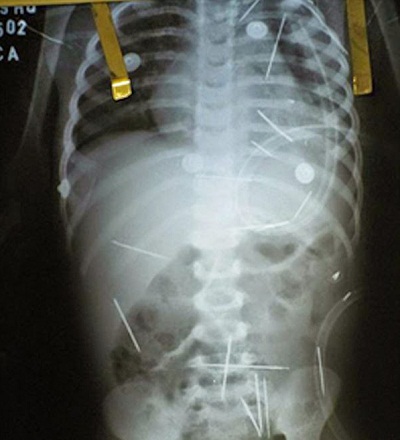

গুরুতর অসুস্থ অবস্থায় ২ বছর বয়সী একটি শিশুকে হাসপাতালে ভর্তি করা হলো। চিকিৎসকরা যখন তাকে পর্যবেক্ষণ করলেন, বিস্ময়ে হতবাক হয়ে গেলেন। এক্সরে রিপোর্টে শিশুটির শরীরের ভেতরের বিভিন্ন অংশে পাওয়া গেল ৫০টির মতো ধাতব সুঁই! এ সুঁইগুলো ছেলেটির শরীরে এমনি এমনি প্রবেশ করেনি! চিকিৎসকদের দৃঢ় বিশ্বাস, এই সুঁইগুলো কেউ একজন খুব সতর্কতার সাথে ধীরে ধীরে অনেকদিন ধরে তার দেহের ভেতরে ঢুকিয়ে দিয়েছে। আরও ভয়ানক ব্যাপার হচ্ছে, ৫০টি সুইয়ের মাঝে ১৭টি ছিল বাচ্চা ছেলেটির পরিপাকতন্ত্রের ভেতরে! অবিলম্বে পুলিশের তদন্ত শুরু হলো। পুলিশের ধারণা, কেউ একজন ব্ল্যাক ম্যাজিক বা কালো জাদুর অংশ হিসেবে ছেলেটির দেহে সুঁই ঢুকিয়ে দিয়েছে। কিন্তু কে করলো এই ভয়াবহ কাজ?

প্রথম সুঁইটি পাওয়া গেল শিশুটির বাম ফুসফুসের ভেতরে। হতবিহবল চিকিৎসকরা এক্সরে করার পর দেখলেন, শিশুটির পেট, গলা, ঘাড় ও পায়ে মোট ৫০ টির মতো সুঁই ঢুকানো হয়েছে। চিকিৎসক ও পুলিশ নিশ্চিত যে, ছেলেটি ভয়াবহ ব্ল্যাক ম্যাজিকের শিকার হয়েছে।

চিকিৎসকরা ছেলেটির ত্বকের নিচে থাকা সুঁই গুলো বের করতে সক্ষম হলেন। কিন্তু ‘লুই সিজার’ বলেন, ‘দেহের বেশ গভীরে থাকা সুঁই গুলো নিয়েই হয়তো শিশুটিকে বাকি জীবন বেঁচে থাকতে হবে। কারণ, অস্ত্রোপচারের মাধ্যমে এগুলো বের করতে গেলে বাচ্চাটির জীবন হুমকির সম্মুখীন হতে পারে।‘ তিনি আরো জানান, এর আগে কখনো তিনি এরকম ঘটনা দেখেননি। তিনি নিশ্চিত, এই সুঁইগুলো শিশুটি নিজ থেকে গিলে ফেলেনি। যদিও এরপর শিশুটি ছিল বিপদমুক্ত, অন্তত সে সময়ের জন্য।